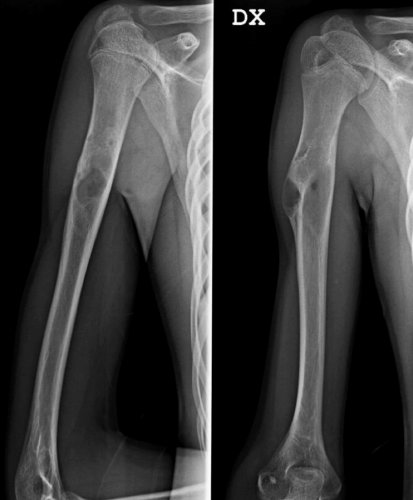

Fig. 2 Controllo post operatorio

Fig. 3 Controllo Rx 1 mese post operatorio

Fig. 4 Controllo Rx 4 mesi post operatorio

Fig. 5 Controllo Rx 1 anno post operatorio